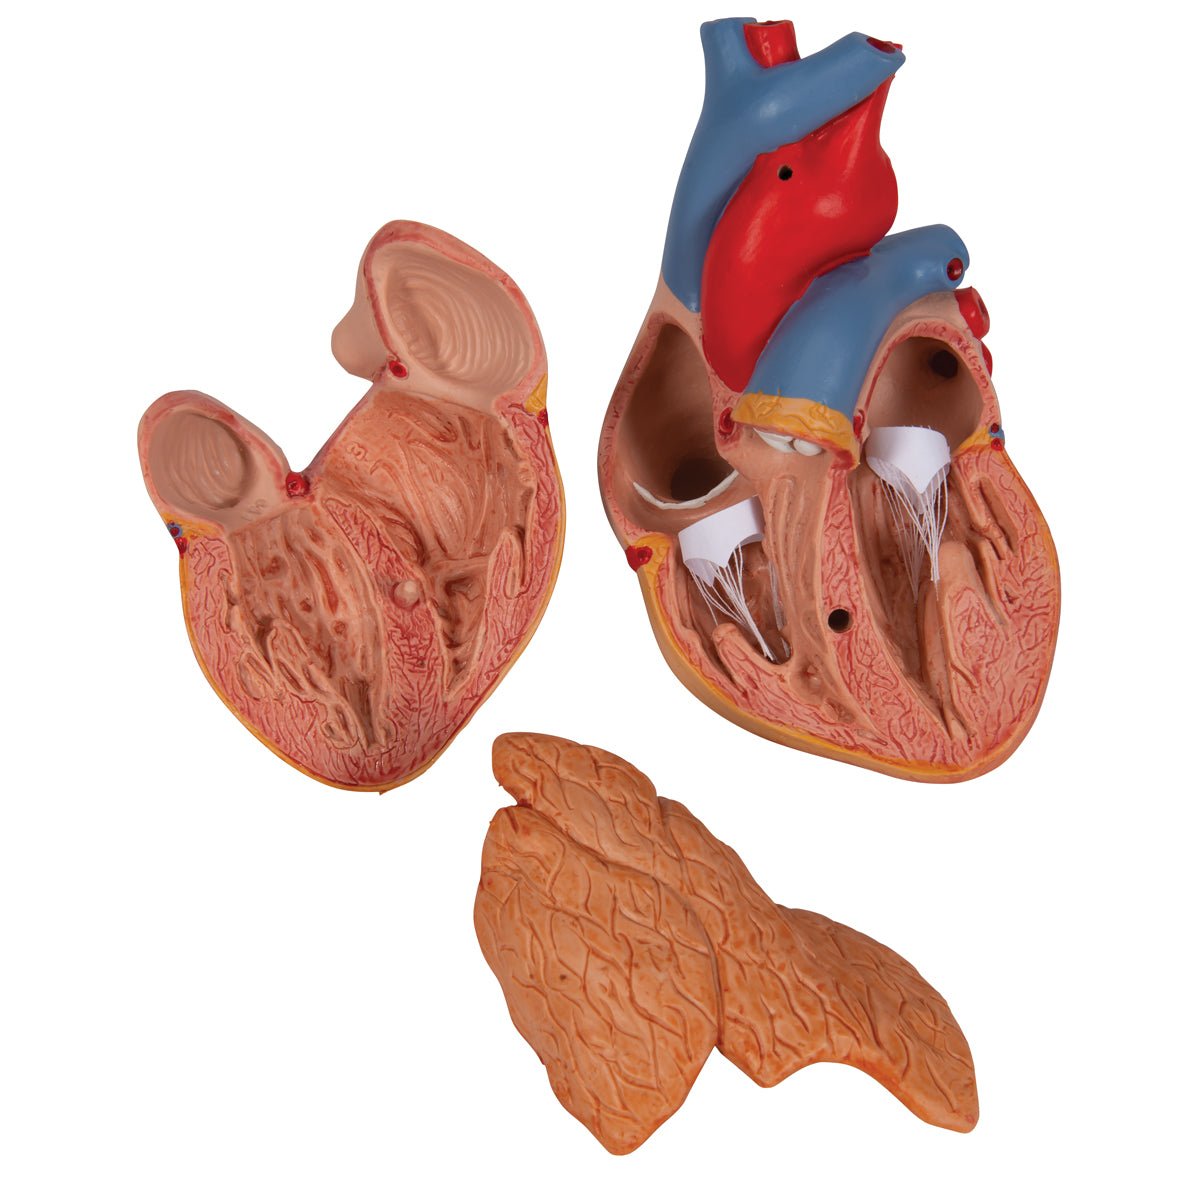

Anatomical models

Selling anatomical models is the mainstay of eAnatomi, although we also spend a lot of resources developing our own anatomical materials such as posters. Anatomical models are used for various purposes and can show both defined tissues, organs and organ systems. Are you looking for a simple model of bone tissue or perhaps an advanced torso model based on MRI technology, you can find it all at eanatomi.com.